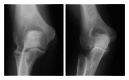

Primary and posttraumatic arthritis of the elbow

Whether degenerative joint disease of the elbow may be the result of primary or posttraumatic etiologies, arthritis of the elbow commonly leads to pain, loss of motion, and functional disability. A detailed history and focused physical examination, in combination with imaging modalities, can help localize the origin of symptoms and help direct treatment. Although nonoperative treatment is the initial therapy for arthritis of the elbow, surgical interventions may provide substantial relief to the appropriately selected patient.